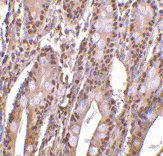

Below: Immunohistochemistry of PHAP III in human small intestine tissue with PHAP III antibody at 2 µg/ml.